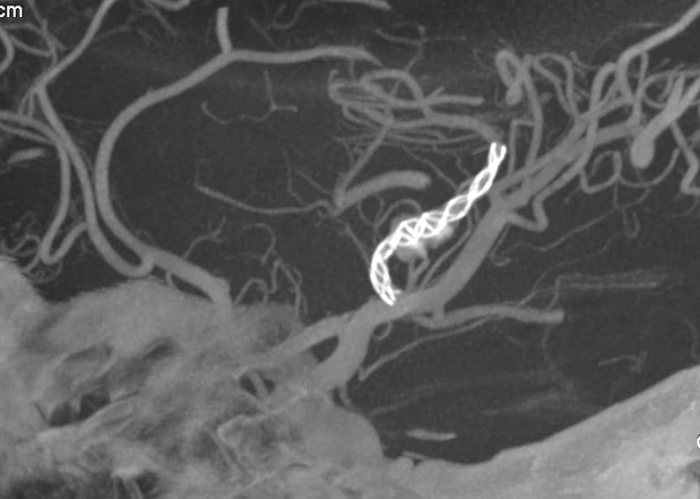

命运的意外转弯,总在不经意间降临。一名17岁的花季少女,本应在憧憬未来的年纪绽放青春,一次常规体检却意外查出了颅内深藏的“不定时炸弹”——右侧大脑中动脉M2段有一颗大小约8mm×6mm的夹层动脉瘤,瘤周血栓环伺,情况危急。而承载血流的载瘤动脉最窄处仅剩1.2mm,如风中细丝般脆弱,随时可能断裂。

患者术前颅内情况复杂

10月10日,临桂院区手术室内,一场精密的“血管拆弹”手术悄然开始。湘雅二医院神经外科喻孟强主任亲自主刀,与驻桂专家郏娇盈博士默契配合。在清晰的影像导航下,喻孟强主任精细操控导丝,在纤细的血管迷宫中稳健前行。最终,那枚承载着生命希望的密网支架被精准送达病变位置,直指深藏的“炸弹”。当造影显示支架完美打开、紧密贴壁,动脉瘤内出现造影剂滞留的那一刻,手术室所有人都松了一口气——这意味着“炸弹”的引信已被成功解除。

术中造影显示支架完美打开、紧密贴壁